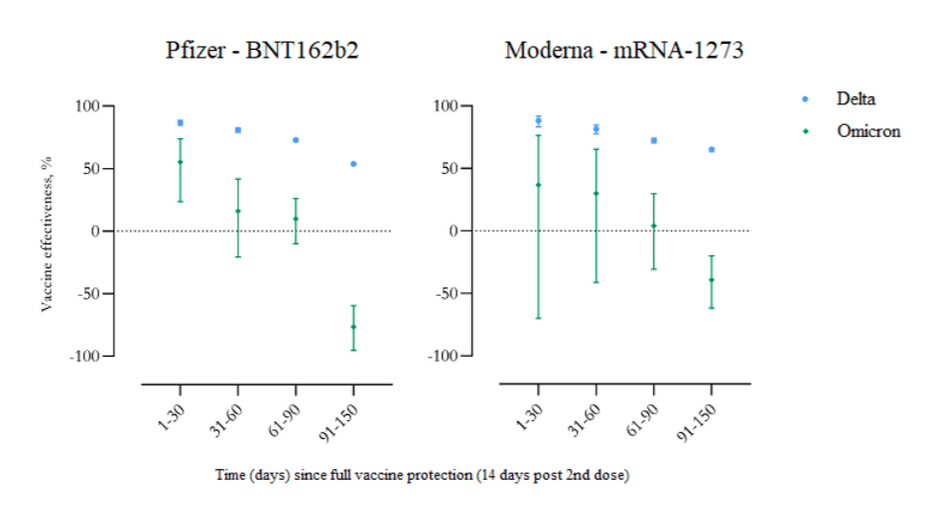

DANISH STUDY: Vaccine effectiveness against SARS-CoV-2 infection with the Delta and Omicron variants, shown separately for the Pfizer and Moderna vaccines.

Negative effectiveness does not mean a person’s protection wears off, though that happens, too. It means that unboosted Covid vaccines make you more vulnerable by suppressing your immune system, accelerating infection and transmission. If vaccinated people don’t get boosted every few months, they will be at greater risk for infection than if they were never vaccinated.

The research out of Denmark shows that compared to the Delta variant, Omicron is far more likely to infect people who are fully vaccinated and boosted than those who are unvaccinated. The study looked at 11,937 Danish households during the month of December 2021. It revealed that to keep the virus at bay vaccinated people will need injections every 30 days. “Why are we encouraging people to get ‘vaccinated’ or ‘boosted’ with a ‘vaccine’ that within a few weeks probably increases their risk of becoming infected with the newly dominant variant of Sars-Cov-2?” asks Berenson.

“If people don’t get boosted as required, they will be MORE vulnerable to Delta and Omicron than if they weren’t vaccinated,” writes Steve Kirsch. “That’s what NEGATIVE vaccine efficacy means.”